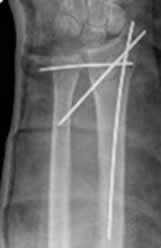

Fig 103. Técnica combinada.

A: Rx AP y B: Rx lateral. Fractura del olécranon, estabilizada con agujas y alambres.